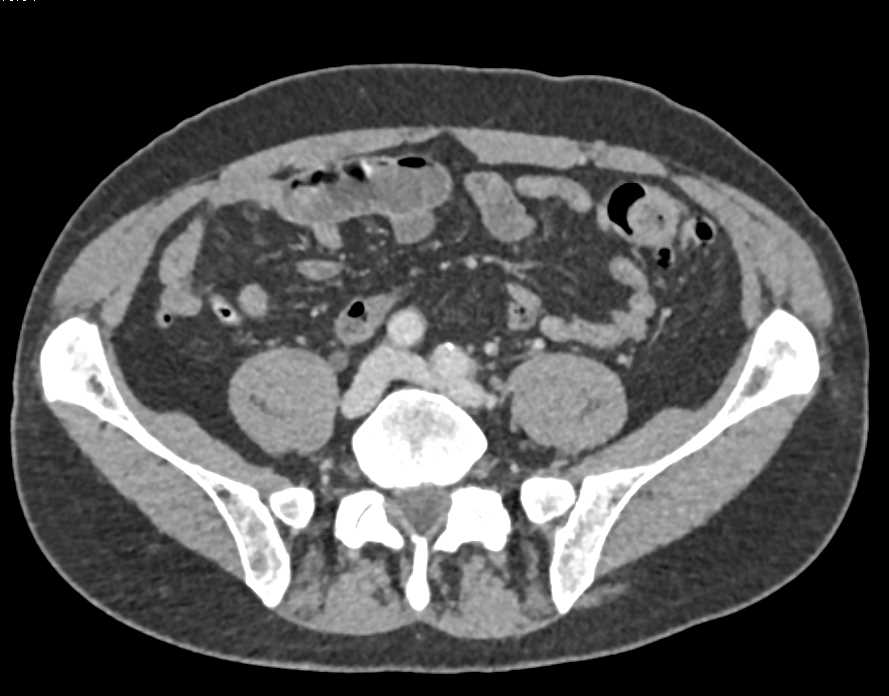

Bladder Cancer Near Right Ureterovesical Junction (UVJ)